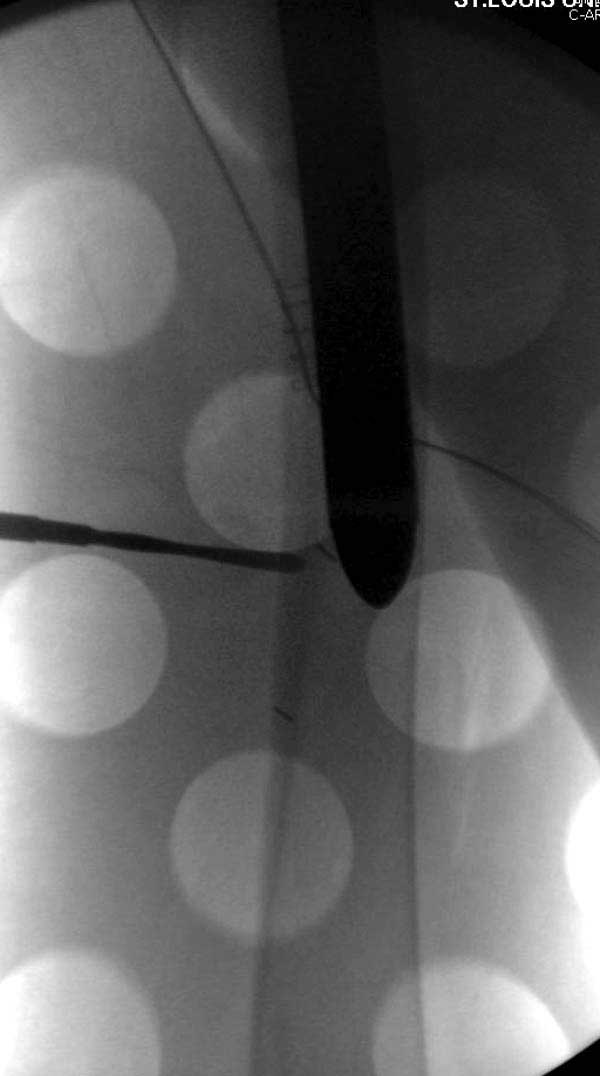

Обычно после чрезвертельных переломов, за исключением молодых, у пожилых остается нестабильность при движении. Часто падают и после 3х мес. в результате падения обнаружен перипротезный перелом (22-23), который зафиксирован Синтез пластиной.

Повторно поступает после двух с половиной лет, где обнаруживается перелом на второй стороне. Немного сложно, но для фиксации выбрали Antegrade InterTan Smith Nephew Nail и с момента фиксации более 3х мес.